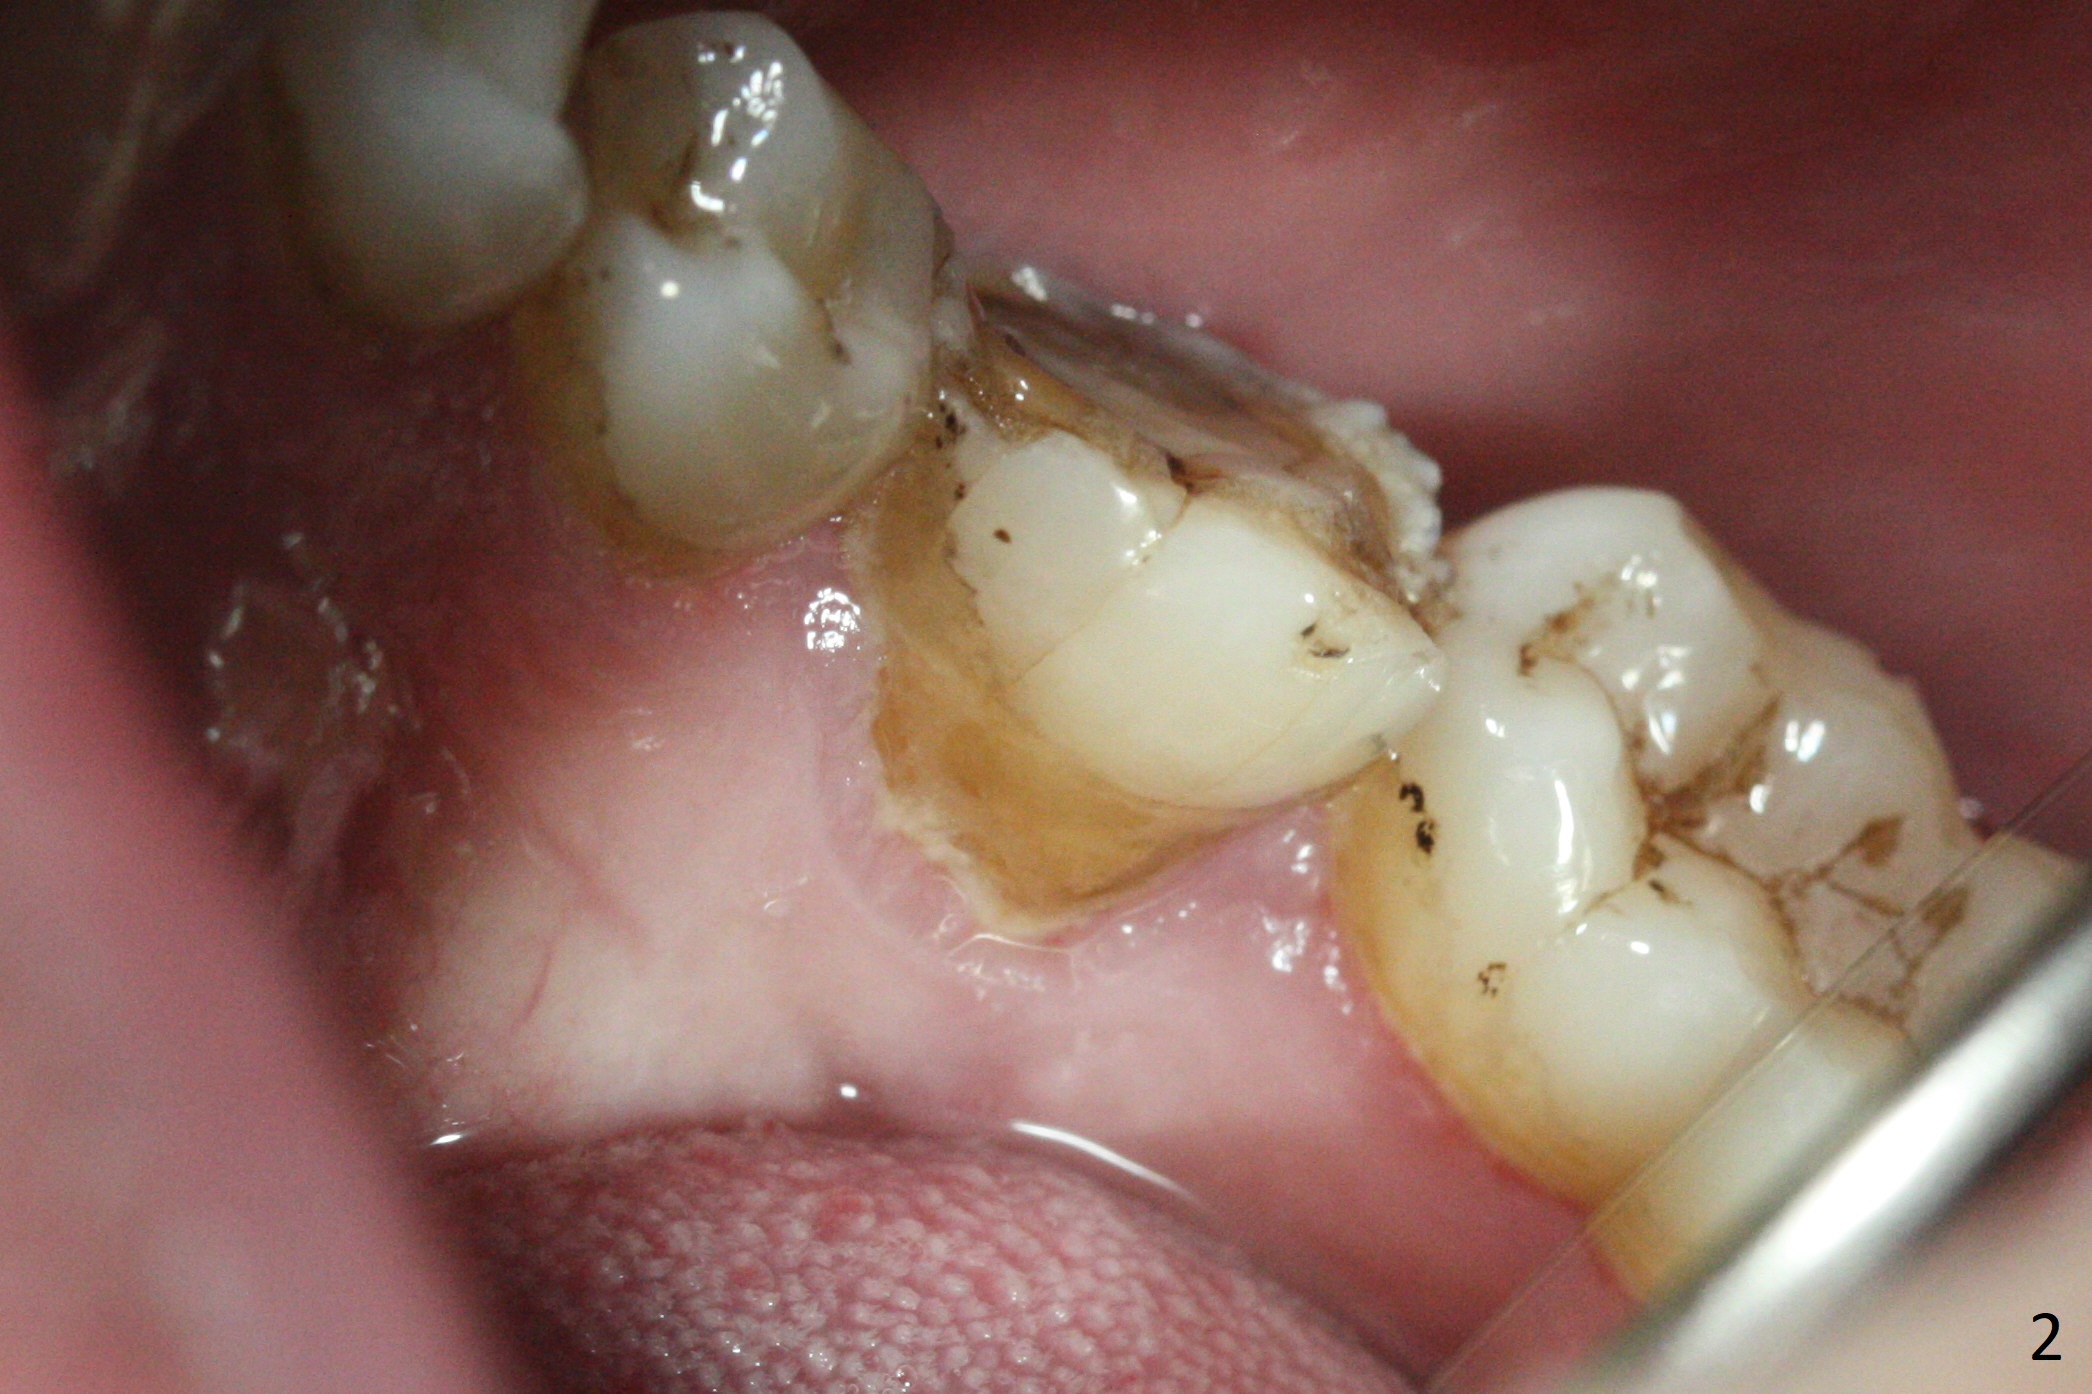

A 34-year-old man has a mobile molar post RCT (Fig.1,3) with lingual gingival recession (Fig.2). Possible bone defect is about 9 mm (Fig.3: purple line). There is approximately 7 mm native bone for primary stability (yellow line). Possible length of the implant to be placed will be 16 mm (9+7). Since the lingual gingiva is recessive (Fig.2), the osteotomy will be initiated more or less in the center of the socket bottom.